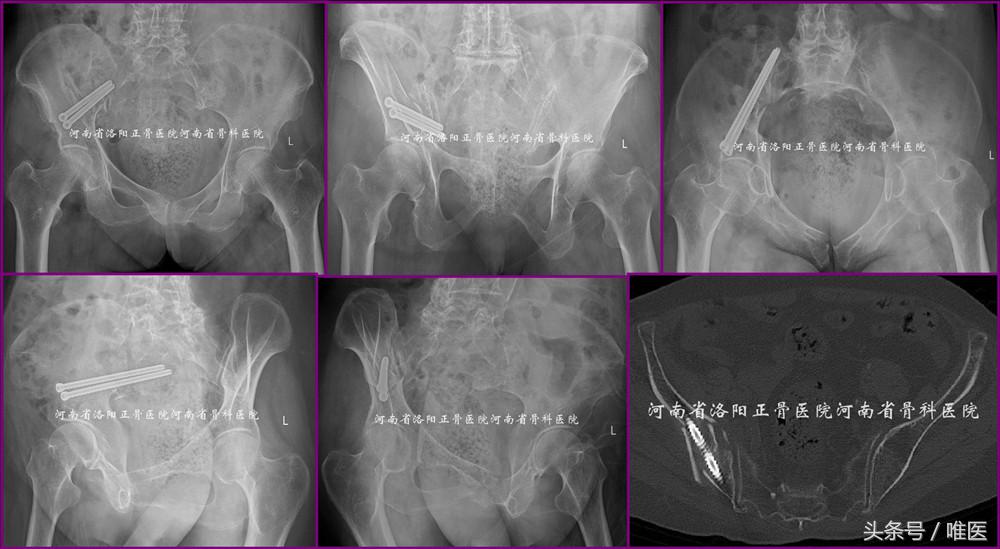

病例1:即本文第一部分所述病例。术前影像资料见图1。术后影像资料见图11。病人术后第一天即坐起活动而有效地降低了卧床并发症。此处给出开篇问题的答案。

图11. LC-II螺钉的经皮置入技术用于治疗LC-II(即OTA-61B2.3)型骨盆骨折。

病例2:一例61岁男性病人,以高处坠落致右髋部疼痛活动受限五天入院。入院诊断:右侧髋臼骨折(OTA-62A3.2)。入院后第三天手术。术后第一天坐起并逐渐拄双拐患侧下肢平足负重下床活动。术后第三天出院。术前及术后影像资料见图12。

图12. LC-II螺钉的经皮置入技术用于治疗髋臼高位前柱骨折(即OTA-62A3.2)。